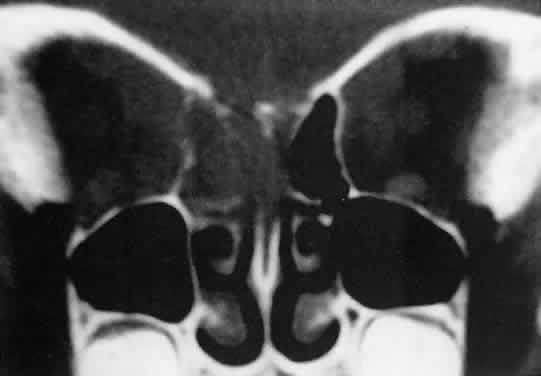

Sporadic North American cases have a less-definitive viral association. These patients differ clinically in their age of presentation (mean, 11 years) and in the usual site of tumor origin (intra-abdominal lymphoid tissue).40,41 Involvement of the facial bones and orbit is less common in the North American cases, but invasion of the orbit from the sinuses may occur42,43 (Fig. 4).

Fig. 4. Burkitt's lymphoma involving the posterior ethmoids, skull base, and both orbital apices in a 5-year-old boy.